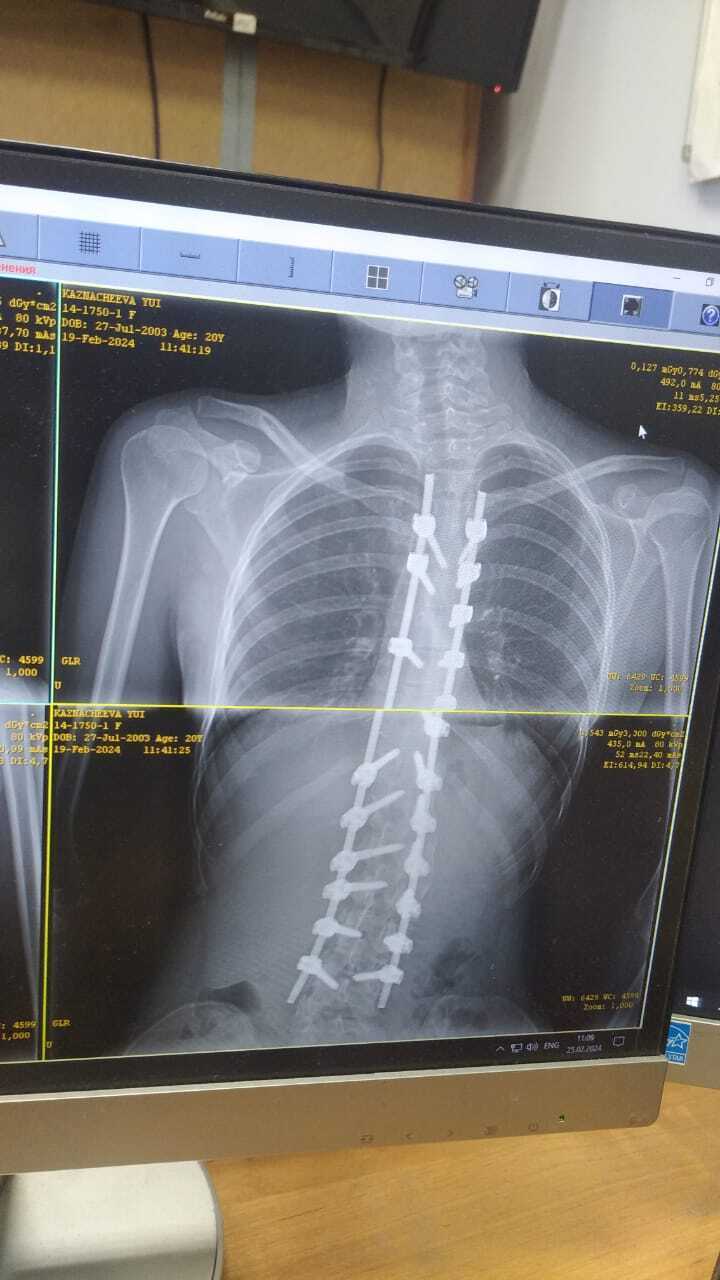

О, я с вами. Делала операцию, так как был сколиоз 4-ой степени. Теперь шрам на всю спину. Говорят, что, примерно, через год шрам станет не таким заметным. Прошло с операции 4 месяца